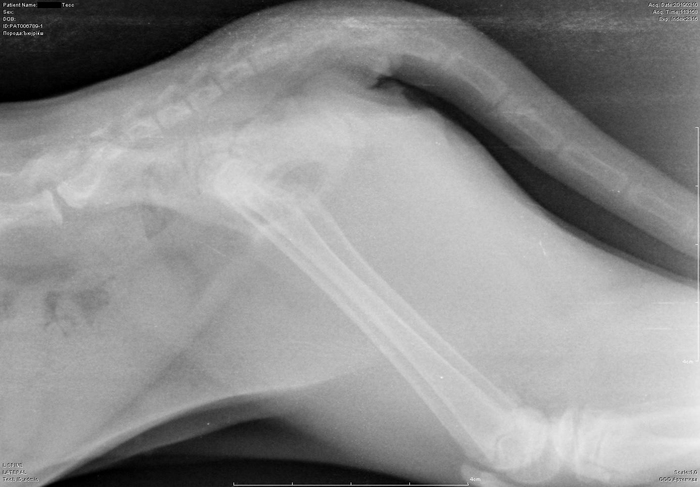

Рентген котенка

Добрый день. Котенок рожден 5 ноября 2018 года, девочка, не привита. Проглистована. Неожиданно в один момент стала припадать на задние ноги. Как бы бережет их и старается не прыгать лишний раз. Свозили два дня назад к ветеринару - всю её прощупал, говорит переломов нет, вывихов тоже. Сделали блокаду ближе в крестцу новокаина, чтобы снять симптомы. Прописал кальций в таблетках Ексел. Сейчас всё примерно так же - лапки задние бережет, но стала по активнее. Прошу специалистов, если такие тут бывают, оценить снимки, т.к. врач ещё кое-что сказал и хотелось бы услышать ваше мнение. Скан расшифровки и д/з потом приложу.

Боковая проекция